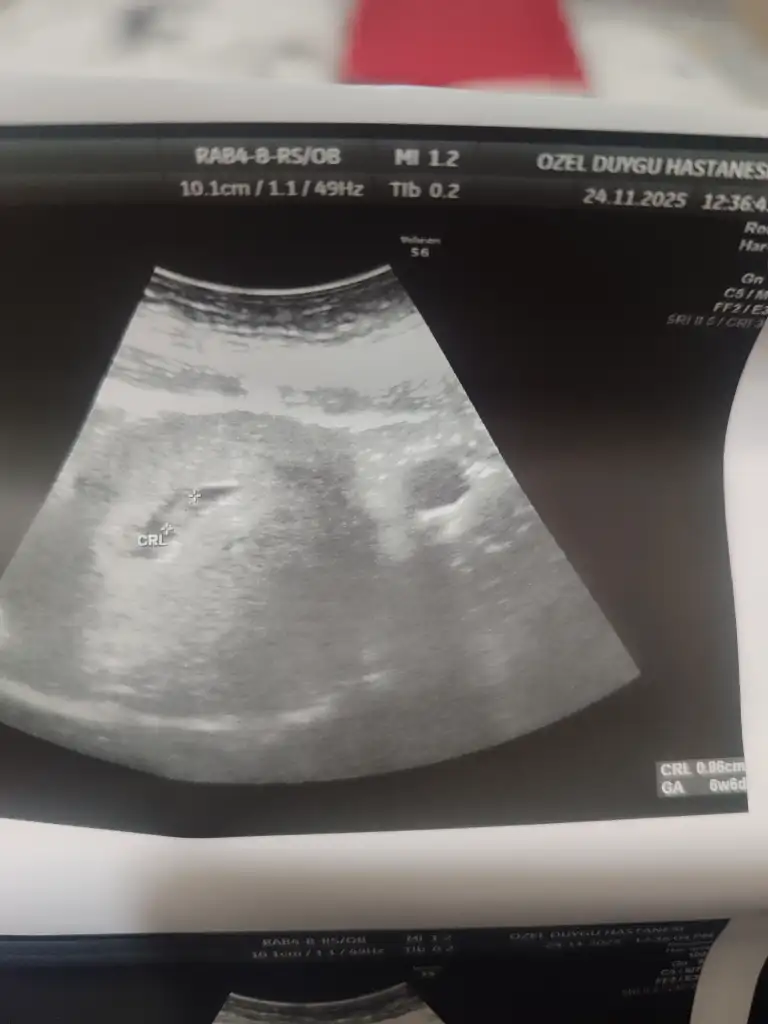

Cok normal canım 5+1 de gittim kese anca göründü küçüktü 4+5 uyumluydu 6+1 de tekrar gittim 1.30 olmuştu kese içi boş gibi demişti doktor yolk saç varla yok arası secilemiyordu vajinal de baktı aynıydı cok erken daha kese küçük dedi haftaya cagırdı 7+1 de gittiğimde hem bebeği hem kalp atısı gördüm cok şükür ogunde 6+6 ile uyumluydu bebiş ultrason görüntülerini ekliyorum fikir olsun için rahat etsinHanımlar 5+2 de doktora gittim kese 15mm idi ama bebeğe dair bişey gözükmedi normal mi doktorum 25mmye kadar görünür dedi biraz korktum açıkçası

Uyy minacık dah büyük hallerinide göreceği daha ayy çok sabırsızlanıyorummCok normal canım 5+1 de gittim kese anca göründü küçüktü 4+5 uyumluydu 6+1 de tekrar gittim 1.30 olmuştu kese içi boş gibi demişti doktor yolk saç varla yok arası secilemiyordu vajinal de baktı aynıydı cok erken daha kese küçük dedi haftaya cagırdı 7+1 de gittiğimde hem bebeği hem kalp atısı gördüm cok şükür ogunde 6+6 ile uyumluydu bebiş ultrason görüntülerini ekliyorum fikir olsun için rahat etsin

İlk foto 7+1 de diğer 2 foto 6+1 den karından ve vajinalden